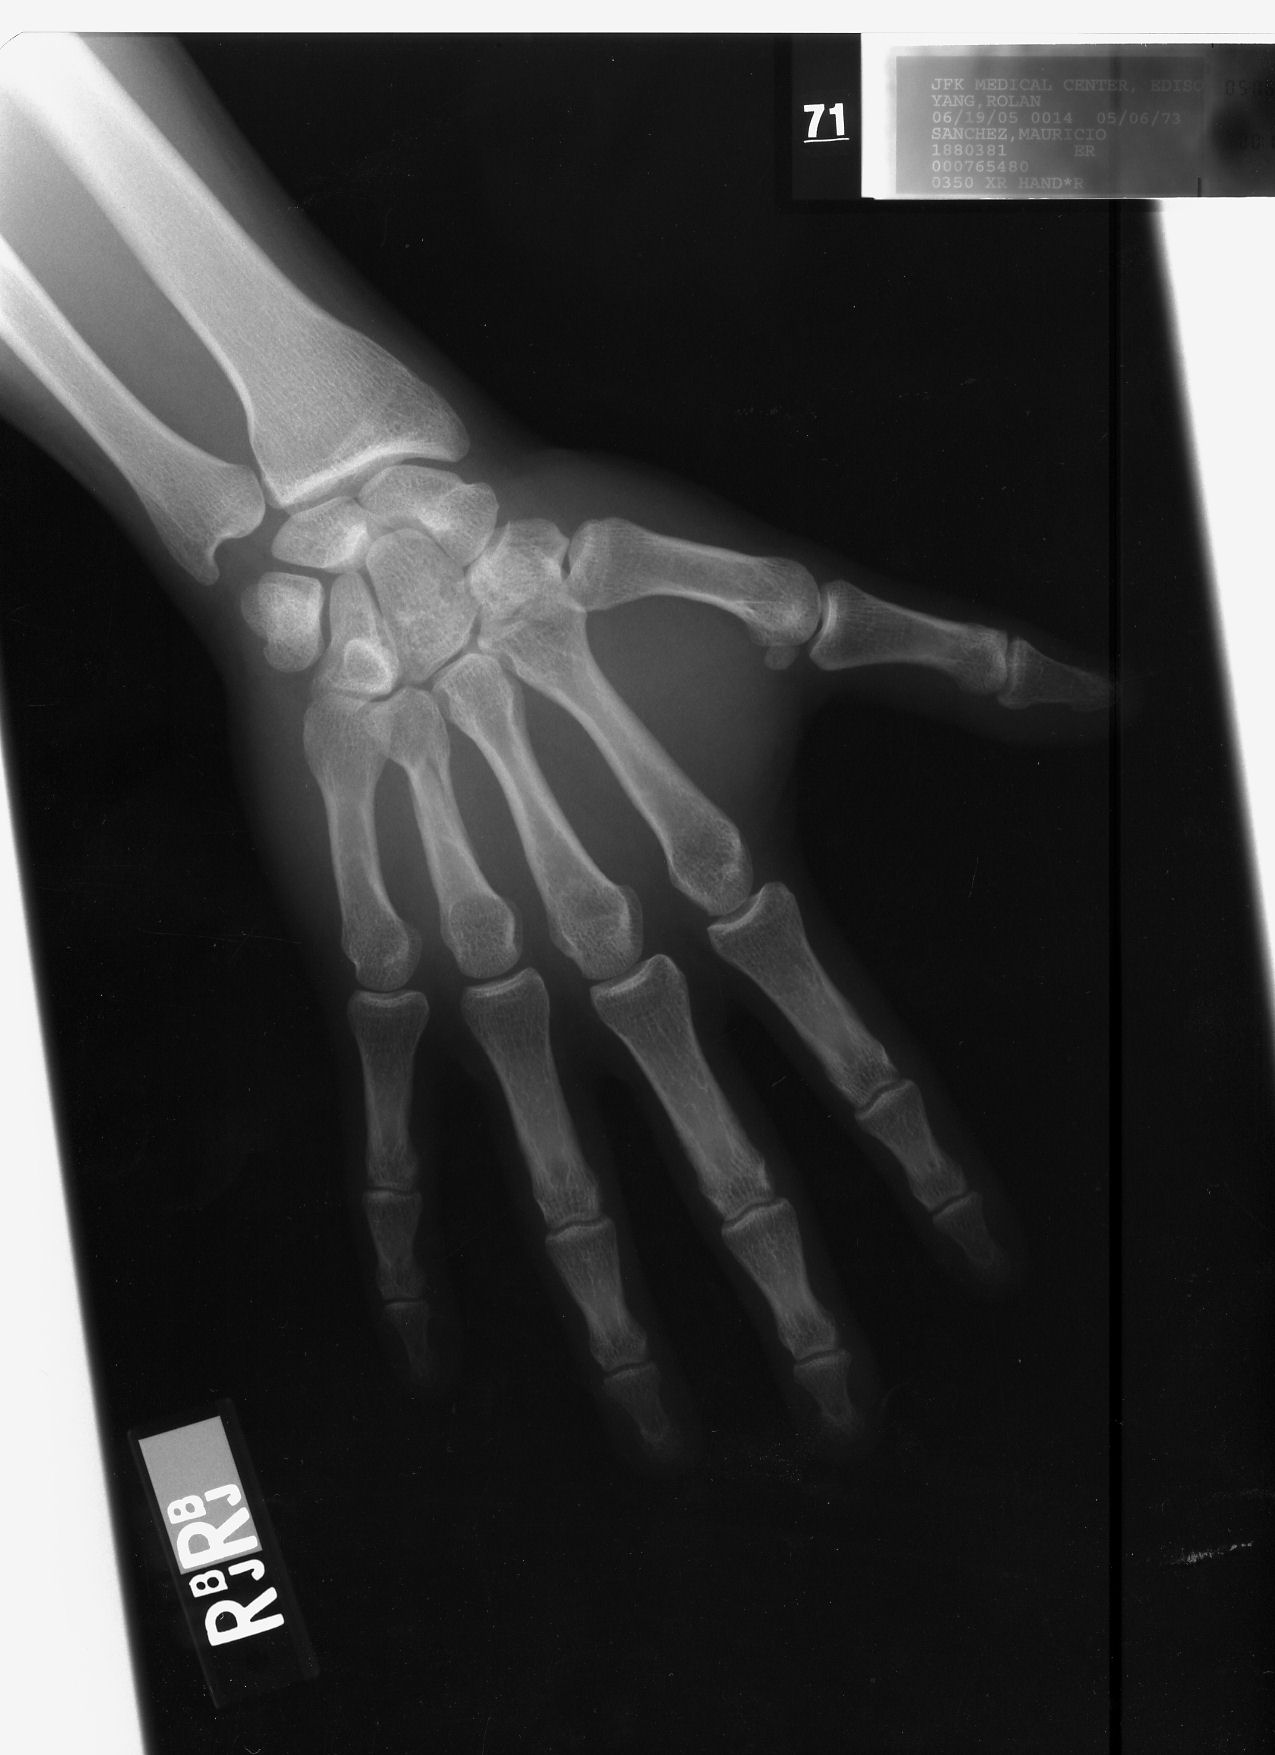

Longitudal fracture fourth metacarpal right hand

6/19/2005 date of injury. Break is not visible at this angle.